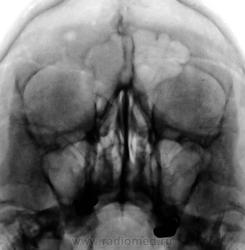

Пол пациента: Женский пол Тип патологии: Другое Область исследования: Челюстно-лицевая область и шея Методы исследования: Rg Направлен ЛОРом. Жалобы на головные боли. https://radiomed.ru/sites/default/files/styles/case_slider_image/public/user/12/2.201310110046.jpg?itok=H9w-gIdU ID:32353 Вс, 13/10/2013 - 11:15 #1 maker4ik Не на сайте Был на сайте: 8 лет 7 месяцев назад Зарегистрирован: 19.10.2011 - 17:49 Публикации: 2682 Да вроде нормально все? Вс, 13/10/2013 - 13:44 #2 И.Бондаренко Не на сайте Был на сайте: 1 день 11 часов назад Зарегистрирован: 13.09.2011 - 22:55 Публикации: 9206 Что за кругляшка справа? Краниограммы не делали? Вс, 13/10/2013 - 17:16 #3 Сергей Кузьминов Не на сайте Был на сайте: 1 год 3 недели назад Зарегистрирован: 06.10.2012 - 15:51 Публикации: 11813 Да вот и я второй день смотрю и не могу понять,что в правой половине лобной кости.Кто-нибудь знает? Вс, 13/10/2013 - 19:11 #4 Катенёв Валенти... Не на сайте Был на сайте: 7 лет 3 недели назад Зарегистрирован: 22.03.2008 - 22:15 Публикации: 54876 И.Бондаренко wrote: Краниограммы не делали? Нет, не делали. Вс, 13/10/2013 - 19:11 #5 Катенёв Валенти... Не на сайте Был на сайте: 7 лет 3 недели назад Зарегистрирован: 22.03.2008 - 22:15 Публикации: 54876 Сергей Кузьминов wrote: Да вот и я второй день смотрю и не могу понять,что в правой половине лобной кости. В лобной кости, или в лобной пазухе? Вс, 13/10/2013 - 19:59 #6 Бородулин М.А. Не на сайте Был на сайте: 9 месяцев 3 недели назад Зарегистрирован: 17.02.2011 - 01:10 Публикации: 1409 Катенёв Валентин Львович wrote: Сергей Кузьминов wrote: Да вот и я второй день смотрю и не могу понять,что в правой половине лобной кости. В лобной кости, или в лобной пазухе? Хороший вопрос)))) Вс, 13/10/2013 - 20:22 #7 алкс Не на сайте Был на сайте: 10 лет 3 недели назад Зарегистрирован: 24.10.2012 - 22:55 Публикации: 2915 Вне пазухи, скорее затылочная кость.Приложения: Втр, 15/10/2013 - 16:02 #8 Nela Не на сайте Был на сайте: 6 лет 1 месяц назад Зарегистрирован: 12.05.2009 - 20:43 Публикации: 1847 Скорее всего венозный выпускник.

Что за кругляшка справа? Краниограммы не делали?

Да вот и я второй день смотрю и не могу понять,что в правой половине лобной кости.Кто-нибудь знает?

В лобной кости, или в лобной пазухе?

Вне пазухи, скорее затылочная кость.

Скорее всего венозный выпускник.